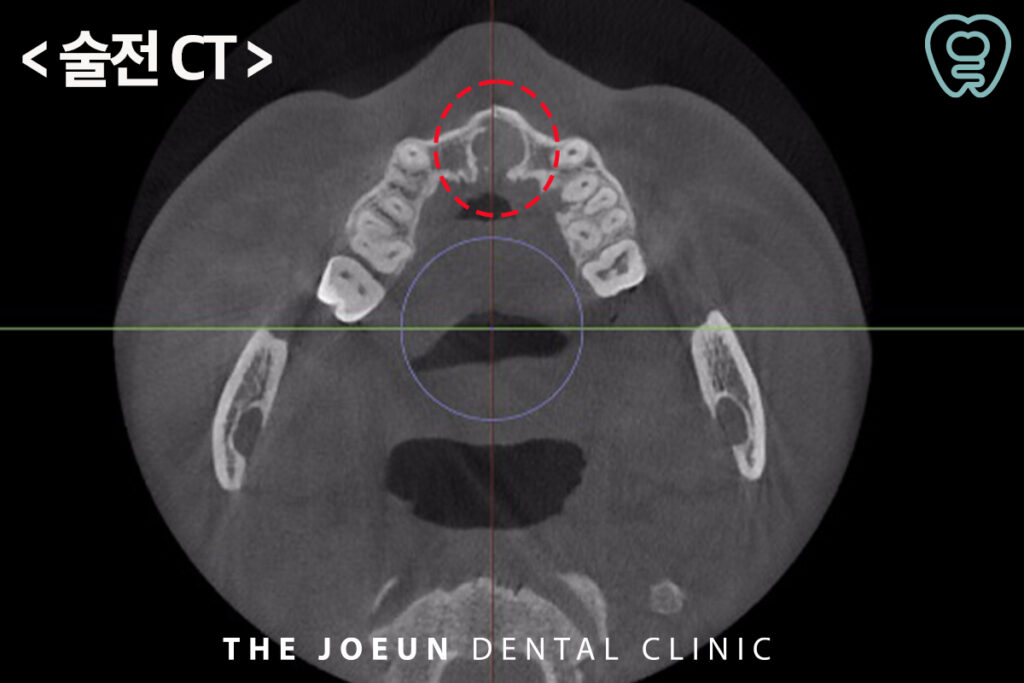

환자분께서는 입천장이 붓는 느낌이 들고 통증이 있다고 하시며 달서구치과에 내원해 주셨는데요. 파노라마를 촬영해 보았을 때, 위쪽 앞니의 뿌리 쪽으로 아주 커다란 물혹이 관찰되었는데요. 더욱 정밀한 진단을 위해 x-ray와 CT 촬영을 모두 진행하였습니다.

모든 방사선 검사에서 경계가 뚜렷이 보이는 낭종이 관찰되었고 낭종적출술을 진행하기로 계획을 수립하였습니다.